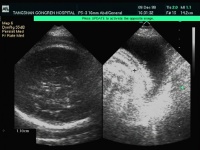

(1)B型超声检查:以单一羊水最大暗区垂直深度(羊水池)(amniotic fluid volume,AFV)测定表示羊水量的方法显示胎儿与子宫壁间的距离增大,超过7cm即可考虑为羊水过多(也有学者认为超过8cm方能诊断羊水过多)。若用羊水指数法(AFI),即孕妇头高30°平卧,以脐与腹白线为标志点,将腹分为4部分测定各象限最大羊水暗区相加而得,国内资料>18cm为羊水过多。而Phelan则认为>20cm方可诊断。经比较AFI显著优于AFD法。羊水过多时,胎儿在宫腔内只占小部分,肢体呈自由体态,漂浮于羊水中,并可同时发现胎儿畸形、双胎等。